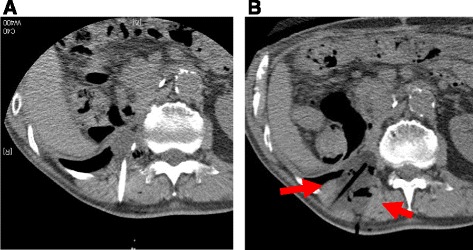

Fig. 1.

Locally recurrent, 3 cm, dedifferentiated liposarcoma in the retroperitoneal paravertebral region 1 year after initial surgery (a, b). c Under CT guidance, air was transperitoneally infused to displace the bowel just adjacent to the recurrent tumor